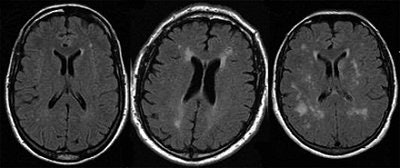

![]() |

| Transverse FLAIR MR (6000/100/2100) images in patients with FD show examples of varying extent of white matter changes (leukoaraiosis, increased signal intensity) according to the FSS, with a score of 2 in a 36-year-old man (left), a score of 5 in a 52-year-old man (middle), and a score of 6 in a 57-year-old woman (right). Figure 1, Gavazzi C, Borsini W, Guerrini L, et al. Subcortical damage and cortical functional changes in men and women with Fabry's disease. Radiology 2006; 241(2): 492-500. |

"The lack of substantial differences in MR imaging findings between men and women in our study confirms that women should not be viewed as simply carriers of the (Fabry's disease) gene and suggests that they could be enrolled in prospective trials investigating treatments for brain changes associated with this disease," the group wrote.

Based on the intergroup analysis, patients with Fabry's disease showed increased activation of the primary sensorimotor complex bilaterally, the contralateral intraparietal sulcus, and the cingulated motor area bilaterally.

Finally, in patients, there was significant correlation between increased activity in the contralateral sensorimotor cortex and FSS. Overall, the researchers found that subcortical white-matter damage due to small-vessel disease was similar in men and women with Fabry's disease. They also noticed a modification in the cortical activation pattern on fMRI during a motor task. Together, these conditions suggest an adaptive role of cortical functional changes to limit the effects of small-vessel disease, they wrote.